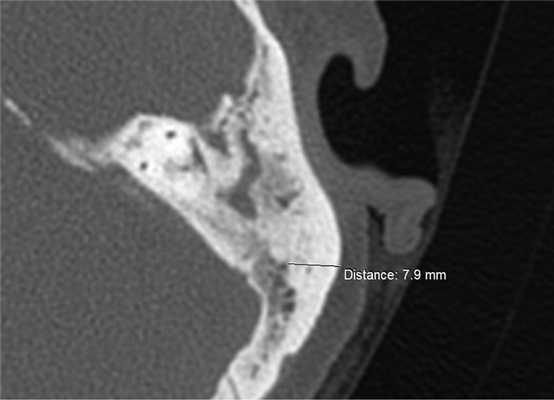

Результаты исследования 60 компьютерных томограмм височных костей больных с ХГСО показали, что наиболее оптимальным участком для взятия стружки аутокости для мастоидопластики является область ВЛ, так как именно в этом месте наружный кортикальный слой кости имеет наибольшую толщину и меньше риск повреждения важных анатомических структур. В среднем толщина наружного кортикального слоя в области височной линии составила 6,4 мм и варьировала от 3,2 мм до 8,3 мм (рис. 2). При толщине наружного кортикального слоя кости менее 4 мм удавалось получить пластический материал только для закрытия глубоких карманов МП. В 6 случаях полученной стружкой аутокости была выполнена полная облитерация М.П. Облитерация М.П. до уровня горизонтального полукружного канала была выполнена у 12 больных. При этом сформирована значительно меньшая по объему послеоперационная полость, что способствовало ее оптимальной эпидермизации. У двух больных вместе с МП был облитерирован эпитимпанум. В 5 случаях удалось взять пластический материал только для облитерации глубоких карманов МП в области верхушки сосцевидного отростка.

Рис. 2. МСКТ левой височной кости, аксиальная проекция. Проекция области височной линии.